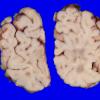

Familial erythrophagic lymphohistiocytosis (4)